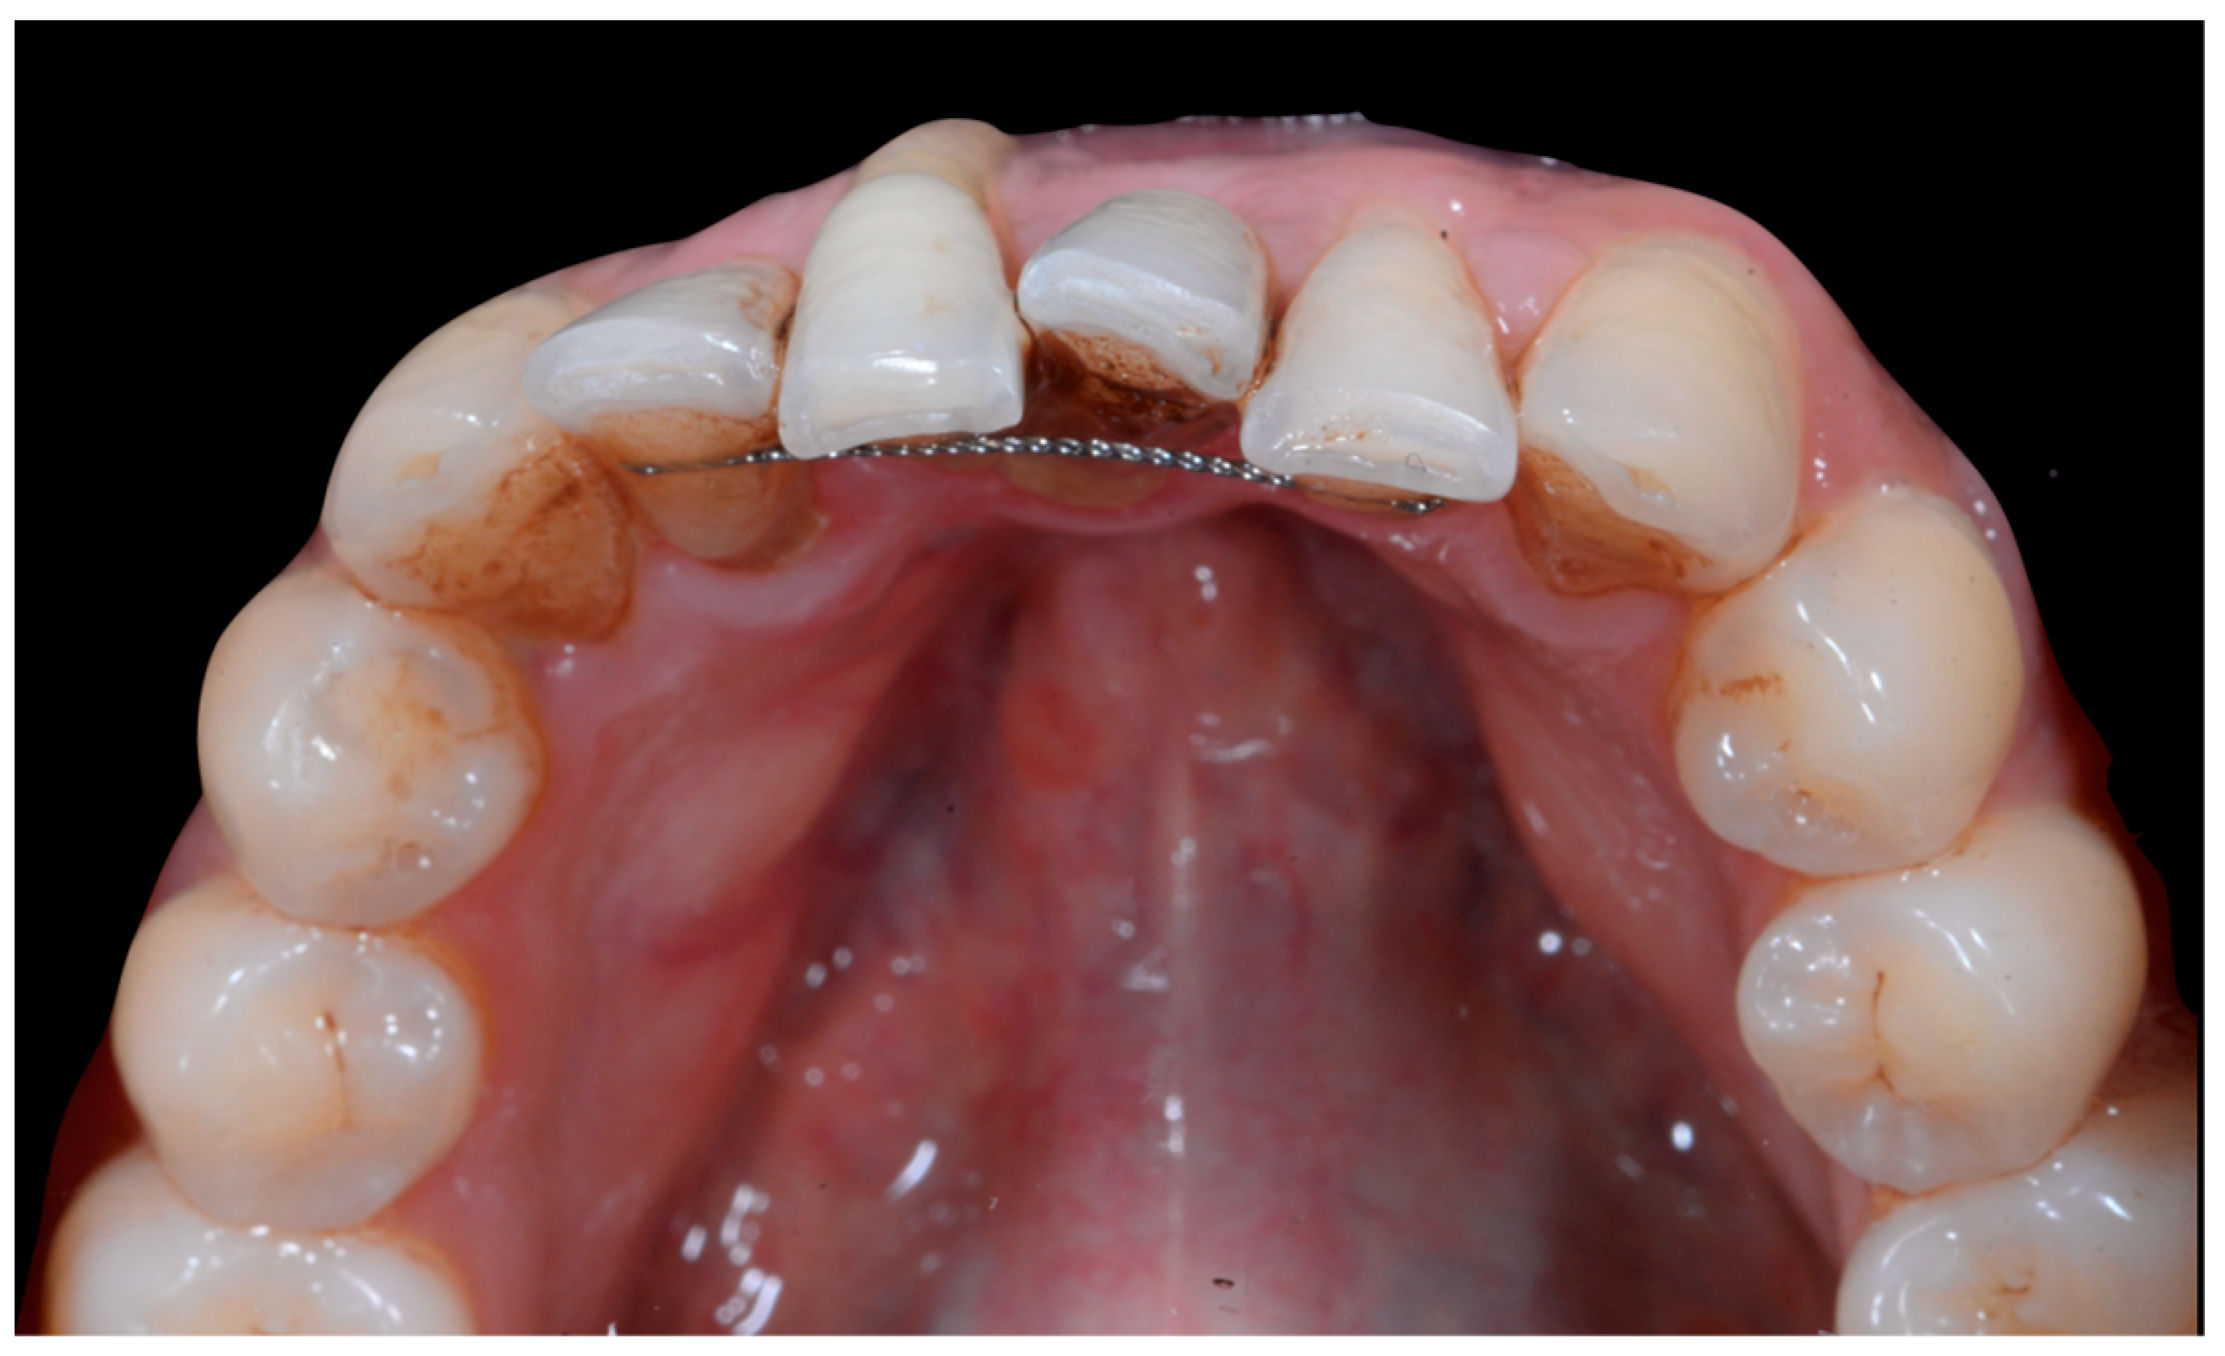

No retainer was present in the maxilla, only a residual mandibular retainer, still bonded to 32 and 42, was visible (Figure 14), as well as incisal crowding and a difference in the visibility of the buccal and root surfaces of 41 compared to the contralaterals. In this extreme clinical situation, a severe and terminal wire syndrome on tooth 41, the “X-effect” type, was observed.

Figure 14.

Severe wire syndrome. Occlusal view.